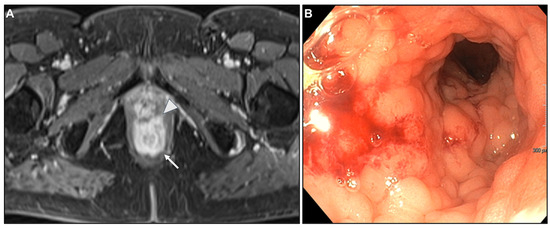

Presacral Fat Tissue and Rectovaginal Septum Infiltration and T2-Weighted Imaging (T2WI) Hypointense Extramural Tumour Component

Intestinal Obstruction